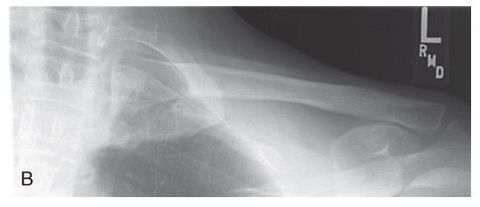

Which projection/position is this? Transthoracic Shoulder ___________________ ribs are blurred out from orthostatic breathing